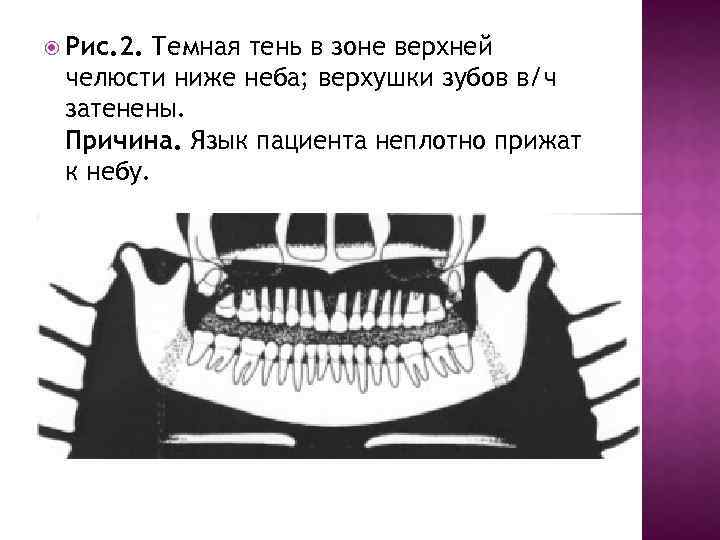

Рис. 2. Темная тень в зоне верхней челюсти ниже неба; верхушки зубов в/ч затенены. Причина. Язык пациента неплотно прижат к небу.